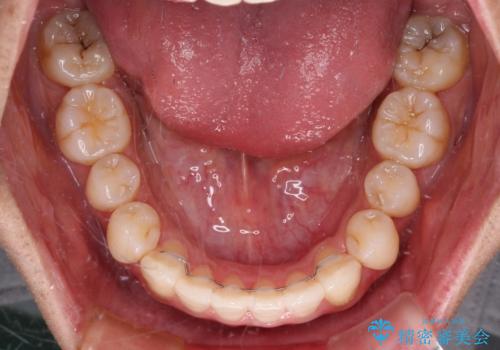

- 全体的なデコボコと、前歯の前に出ている感じを気にして来院された患者様です。

患者様と相談の上、非抜歯にてインビザラインを用いて矯正治療を行うこととし、IPR(歯と歯の間)並びに歯列全体の後方移動により口元の突出感の改善することとしました。

お仕事が忙しい方で、装着時間が不足したり、定期的な通院ができなかったりと、自己管理が重要なインビザラインによる矯正治療が長期化する要因が重なり、5年ほどの期間を要しました。